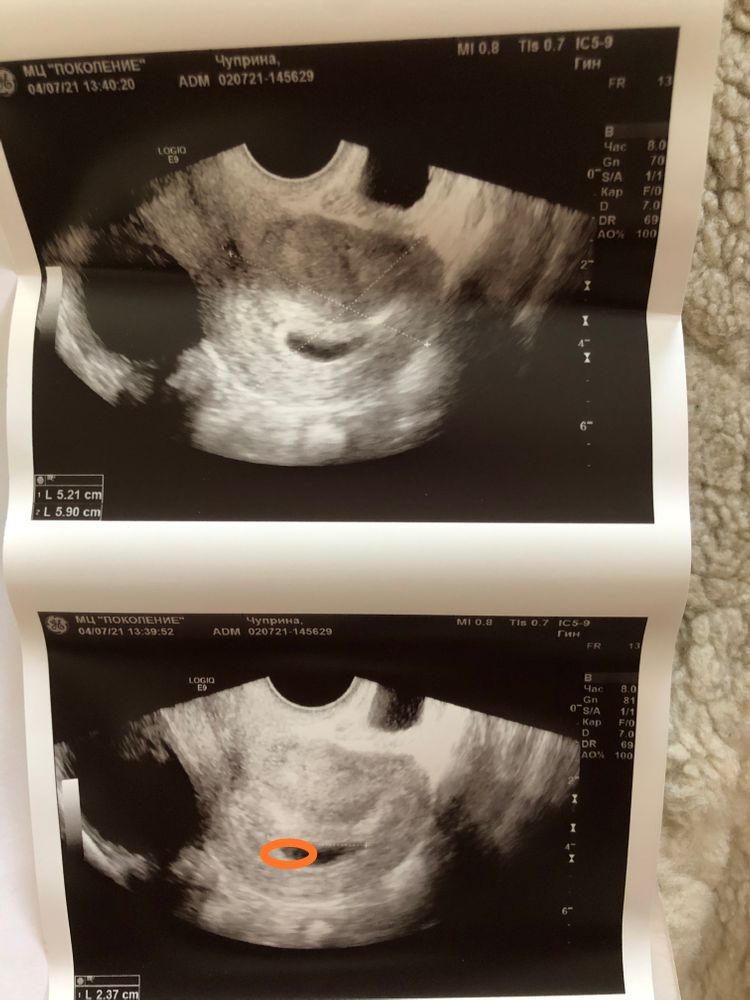

квитка, а есть снимок УЗИ?

Марина, Изображение

квитка, пя точно не пустое,да и срок у вас маленький, ещё и 6 полных недель нет

квитка, да,на вашем снимке если правильно разобралась,вот он похоже Изображение

Olesya , я знаю как выглядит,у автора фото нечёткое,если увеличить похоже на колечко